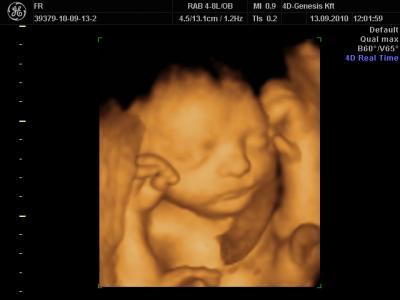

Guten Abend liebe Mitkugelnden, nun bin ich wieder zurück von meinen Eltern. Ich habe während meines Besuches die Gelegenheit genuzt, das Angebot eines 3D Studios in Anspruch zu nehmen. In Budapest gibt davon zuhauf und die Preise sind im Vergleich zu Deutschland wirklich günstig. Es war einfach toll! Wir konnten eine Stunde lang unser Baby aus allen möglichen Winkeln in 3/4 D anschauen. Er war die ganze Zeit wach und machte nur Blödsinn, Fuß in den Mund stecken, mit der Nabelschnur spielen, Grimassen ziehen etc. Es war eine tolle Erfahrung. Ich füge ein Bildchen bei, wünsche Euch allen einen schönen Abend, Reka

Bild zu Baby-TV - super schön - Forum für Dezember - Mamis